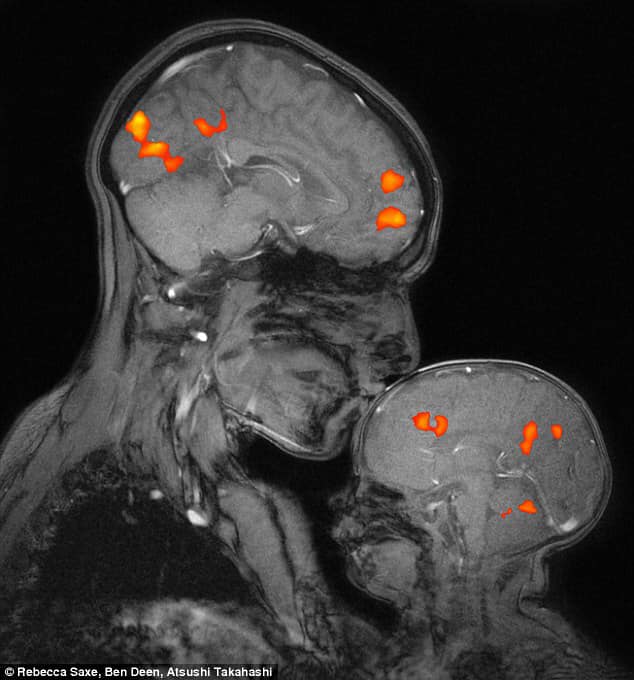

La scienziata ha fatto una risonanza magnetica che ha ripreso l'istante in cui dava un bacio sulla fronte di suo figlio, di soli 2 mesi. La fotografia è impressionante e decisamente commovente: il bacio ha attivato contemporaneamente le stesse aree del cervello nella mamma e nel bambino, a conferma che l'accudimento e l'amore creano un vero e proprio ponte emotivo tra chi offre amore e chi lo riceve. Un ponte emotivo che ha ripercussioni benefiche su specifiche aree del cervello e che attiva il cosiddetto processo di rispecchiamento emotivo. Questo sarebbe anche il motivo per cui spesso un bacio della mamma su un ginocchio sbucciato è più efficace di un cerotto!

Guidetti ha anche ricordato che proprio questo ultimo studio del MIT conferma quanto già si ipotizzava: la carenza affettiva da parte dei genitori può provocare disturbi di internalizzazione, di cui il mal di testa è una delle massime espressioni, soprattutto se questa carenza avviene nel periodo tra i 2 e i 5 anni quando il bambino costruisce la Theory of Mind, cioè la capaictà di comprendere le azioni e le emozioni dell'altro e reagire di conseguenza.